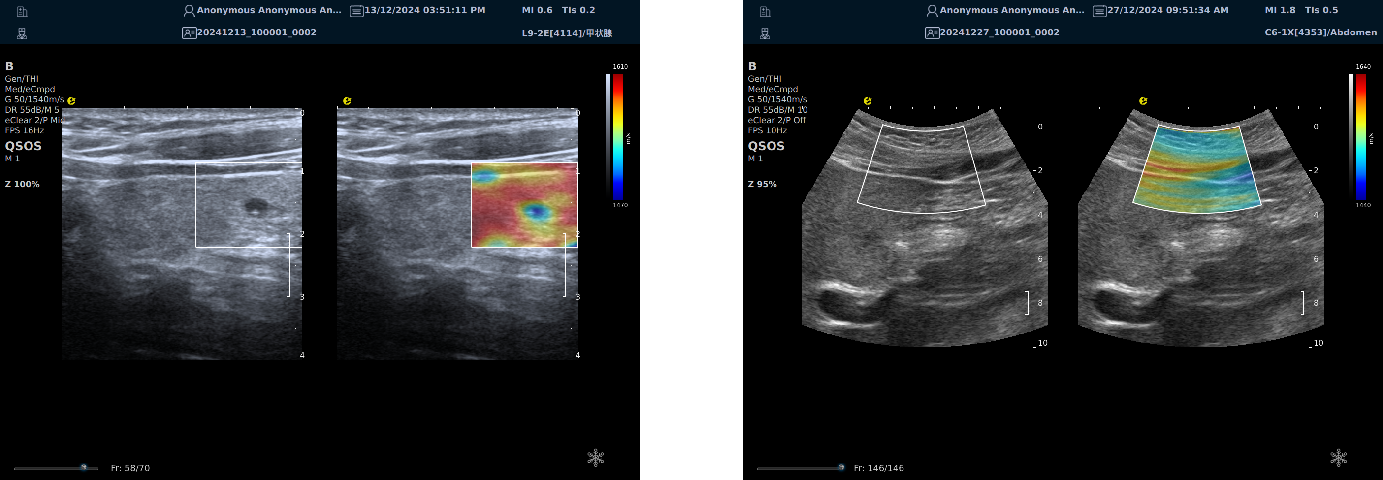

声速定量成像

作为一种新兴的超声成像技术,为医学诊断和生物医学研究提供了重要的信息。利用声波在不同组织中的传播速度差异,测量每个部位的声速,并将测出来的声速通过彩色编码进行显示,生成反映组织物理特性的图像(即声速成像图),对于疾病的早期检测、诊断和治疗评估具有重要的意义。

声速定量成像给临床提供了全新的诊疗思路及工具。